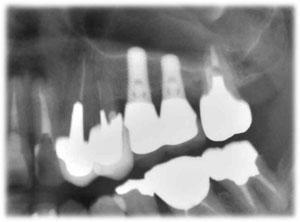

| 術前 | ソケットリフト手術 | 術後2年歯根周囲骨造成良好 |